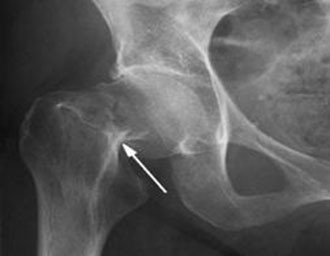

Ниже рентгенограммы ложного сустава, асептического некроза, перелома шейки бедра и чрезвертельного перелома.

Из-за особенностей кровообращения шейка бедра как правило не срастается даже у молодых (исключение молодой возраст и вколоченный перелом), без оперативного вмешательства, то бишь эндопротезирования тазобедренного сустава, есть шанс "встать на ноги", если в столь преклонном возрасте не добьют осложнения, но это будет асептический некроз головки бедренной кости, образование ложного сустава, укорочение конечности, нога перестаёт быть опорной, поэтому до конца жизни ходьба на костылях/ходунках. А вот если сломаться чуть дистальнее (ниже), то чрезвертельные переломы уже намного охотнее срастаются.